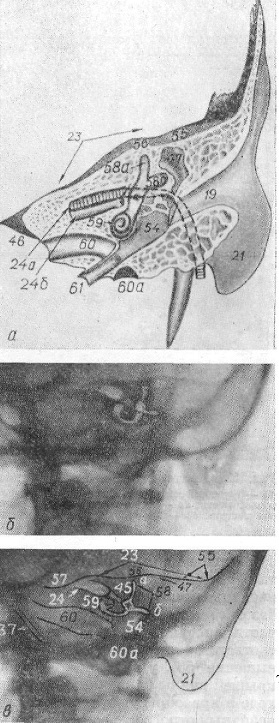

Анатомия сосцевидного отростка